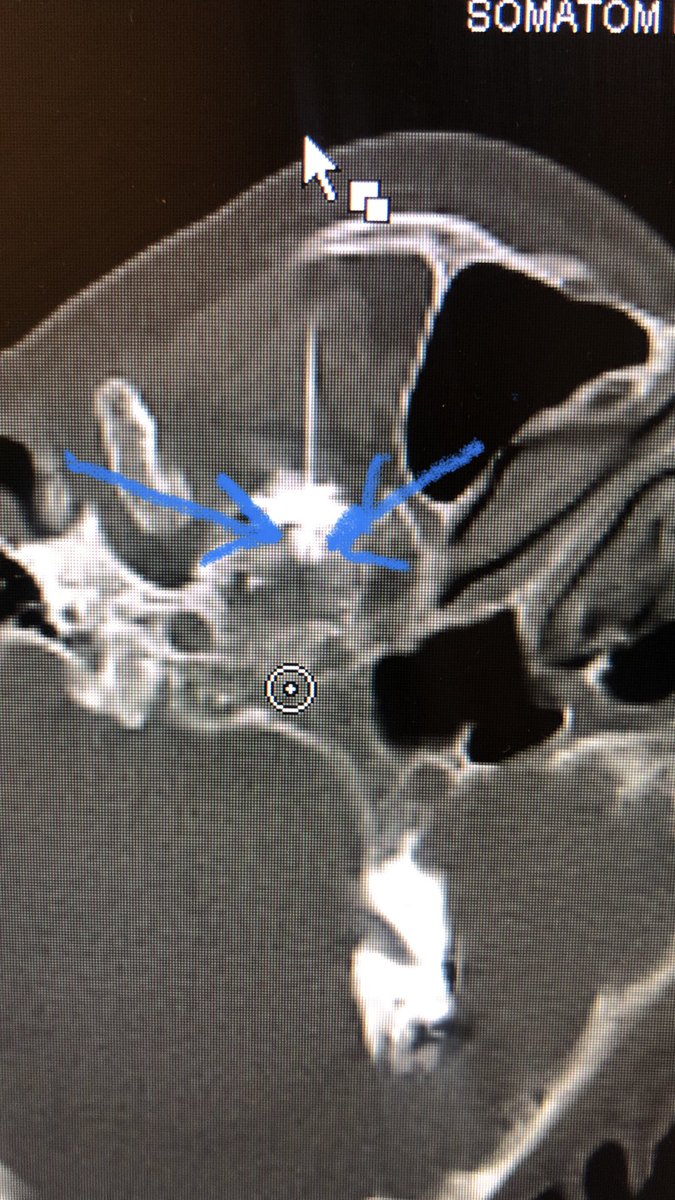

CT is an underutilized modality for treating #Trigeminal #neuralgia with a nerve block. You can see the contrast going just into the the foramen ovale and around the gasserian ganglion (blue arrows)

dougbeall's tweet image. CT is an underutilized modality for treating #Trigeminal #neuralgia with a nerve block. You can see the contrast going just into the the foramen ovale and around the gasserian ganglion (blue arrows)